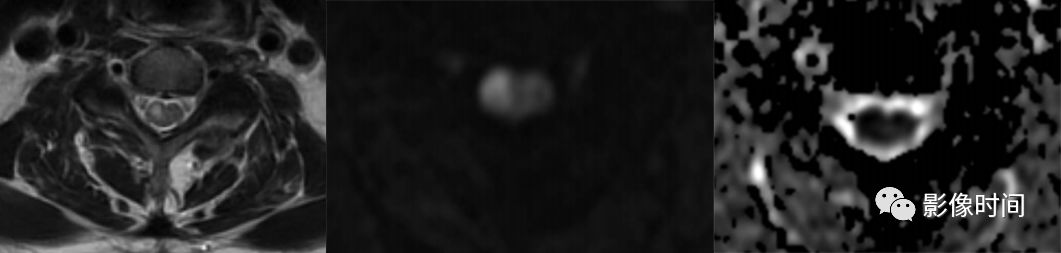

脊髓梗死(spinal infarction),各种原因(比如动脉夹层、椎体术后、纤维软骨栓塞等等)导致的脊髓供血动脉缺血,脊髓前动脉最多见

前 2/3 脊髓(脊髓前动脉);双侧灰质前角(脊髓前动脉);后索(脊髓后动脉)

T2WI 高信号病灶,DWI 呈高信号,ADC 呈低信号

轴位「鹰眼征」

脊髓前动脉梗死导致双侧灰质前角梗死(鹰眼征),矢状位呈线样,DWI 提示细胞毒性水肿

脊髓前动脉梗死导致脊髓前 2/3 梗死,DWI 提示细胞毒性水肿

脊髓后动脉梗死导致脊髓后索梗死,DWI 提示细胞毒性水肿